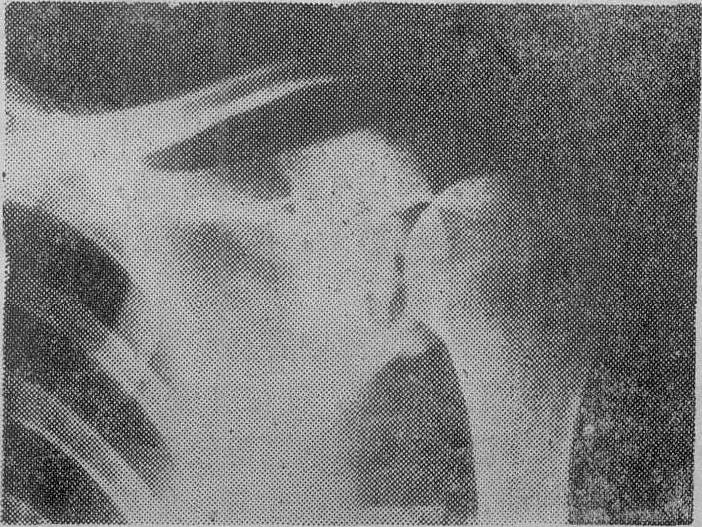

X线检查对本病非常重要。松质骨中心型结核早期可见局部骨小梁模糊是谓磨砂玻璃样改变,稍晚可见死骨游离,死骨一般呈椭圆形,密度比周围骨质稍高。死骨吸收后可见骨空洞,洞壁骨质稍致密(图1)。松质骨边缘型结核可见局限性溶骨性破坏,局部多无死骨或仅有细碎死骨,缺损边缘稍致密。密质骨结核可见髓腔内溶骨性破坏和骨膜新骨形成(图2)。干骺部结核则兼备松质骨和密质骨结核的特点(图3)。长期混合感染则骨质明显硬化。单纯滑膜结核仅见骨质疏松和局部软组织肿脓。早期全关节结核除局部骨质疏松和软组织肿胀外,尚可见关节小部分模糊或破坏。晚期全关节结核则关节边缘大部分模糊、破坏,关节间隙狭窄或消失,常合并脱位或畸形。除上述骨与关节改变外,有时尚能见到寒性脓肿影象,晚期脓肿可发生钙化。

图1 肩胛盂中心型骨结核可见溶骨性破坏及死骨